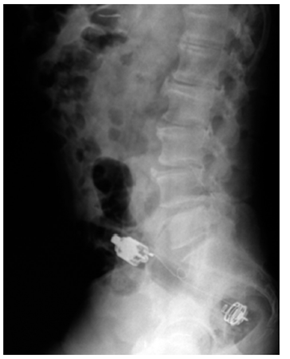

Las radiografías (Rx) de abdomen son los exámenes de primera mano para hacer el abordaje inicial; estas permiten localizar el objeto, estimar el tamaño y determinar la cantidad. Se requiere usar una proyección anteroposterior y otra lateral para dar una localización más exacta (Figuras 3 y 4). Los objetos como el metal o grava son más densos que los tejidos que los rodean y permiten una mejor visualización en las Rx. Los materiales orgánicos que poseen una densidad similar a los tejidos humanos pueden no ser observados en las diferentes proyecciones 9. La no observación de un cuerpo extraño en la Rx no descarta la presencia del mismo.

Según las características del cuerpo extraño, puede usarse la clasificación de fácil agarre, dentro de los que se encuentran elementos cortopunzantes pequeños, huesos, espinas y fálicos como los consoladores, vibradores, velas, vegetales y frutas (Figura 1). Los de difícil agarre corresponden a envases, botellas, tarros, frascos, esferas, bombillos, entre otros (Figura 2).